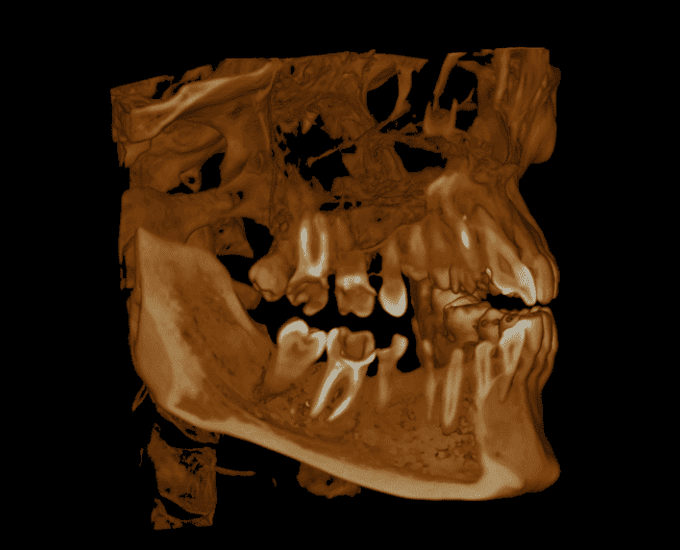

View from anywhere

Volume example 1 Volume example 2 Volume example 3 Volume example 4 Volume example 5 Volume example 6